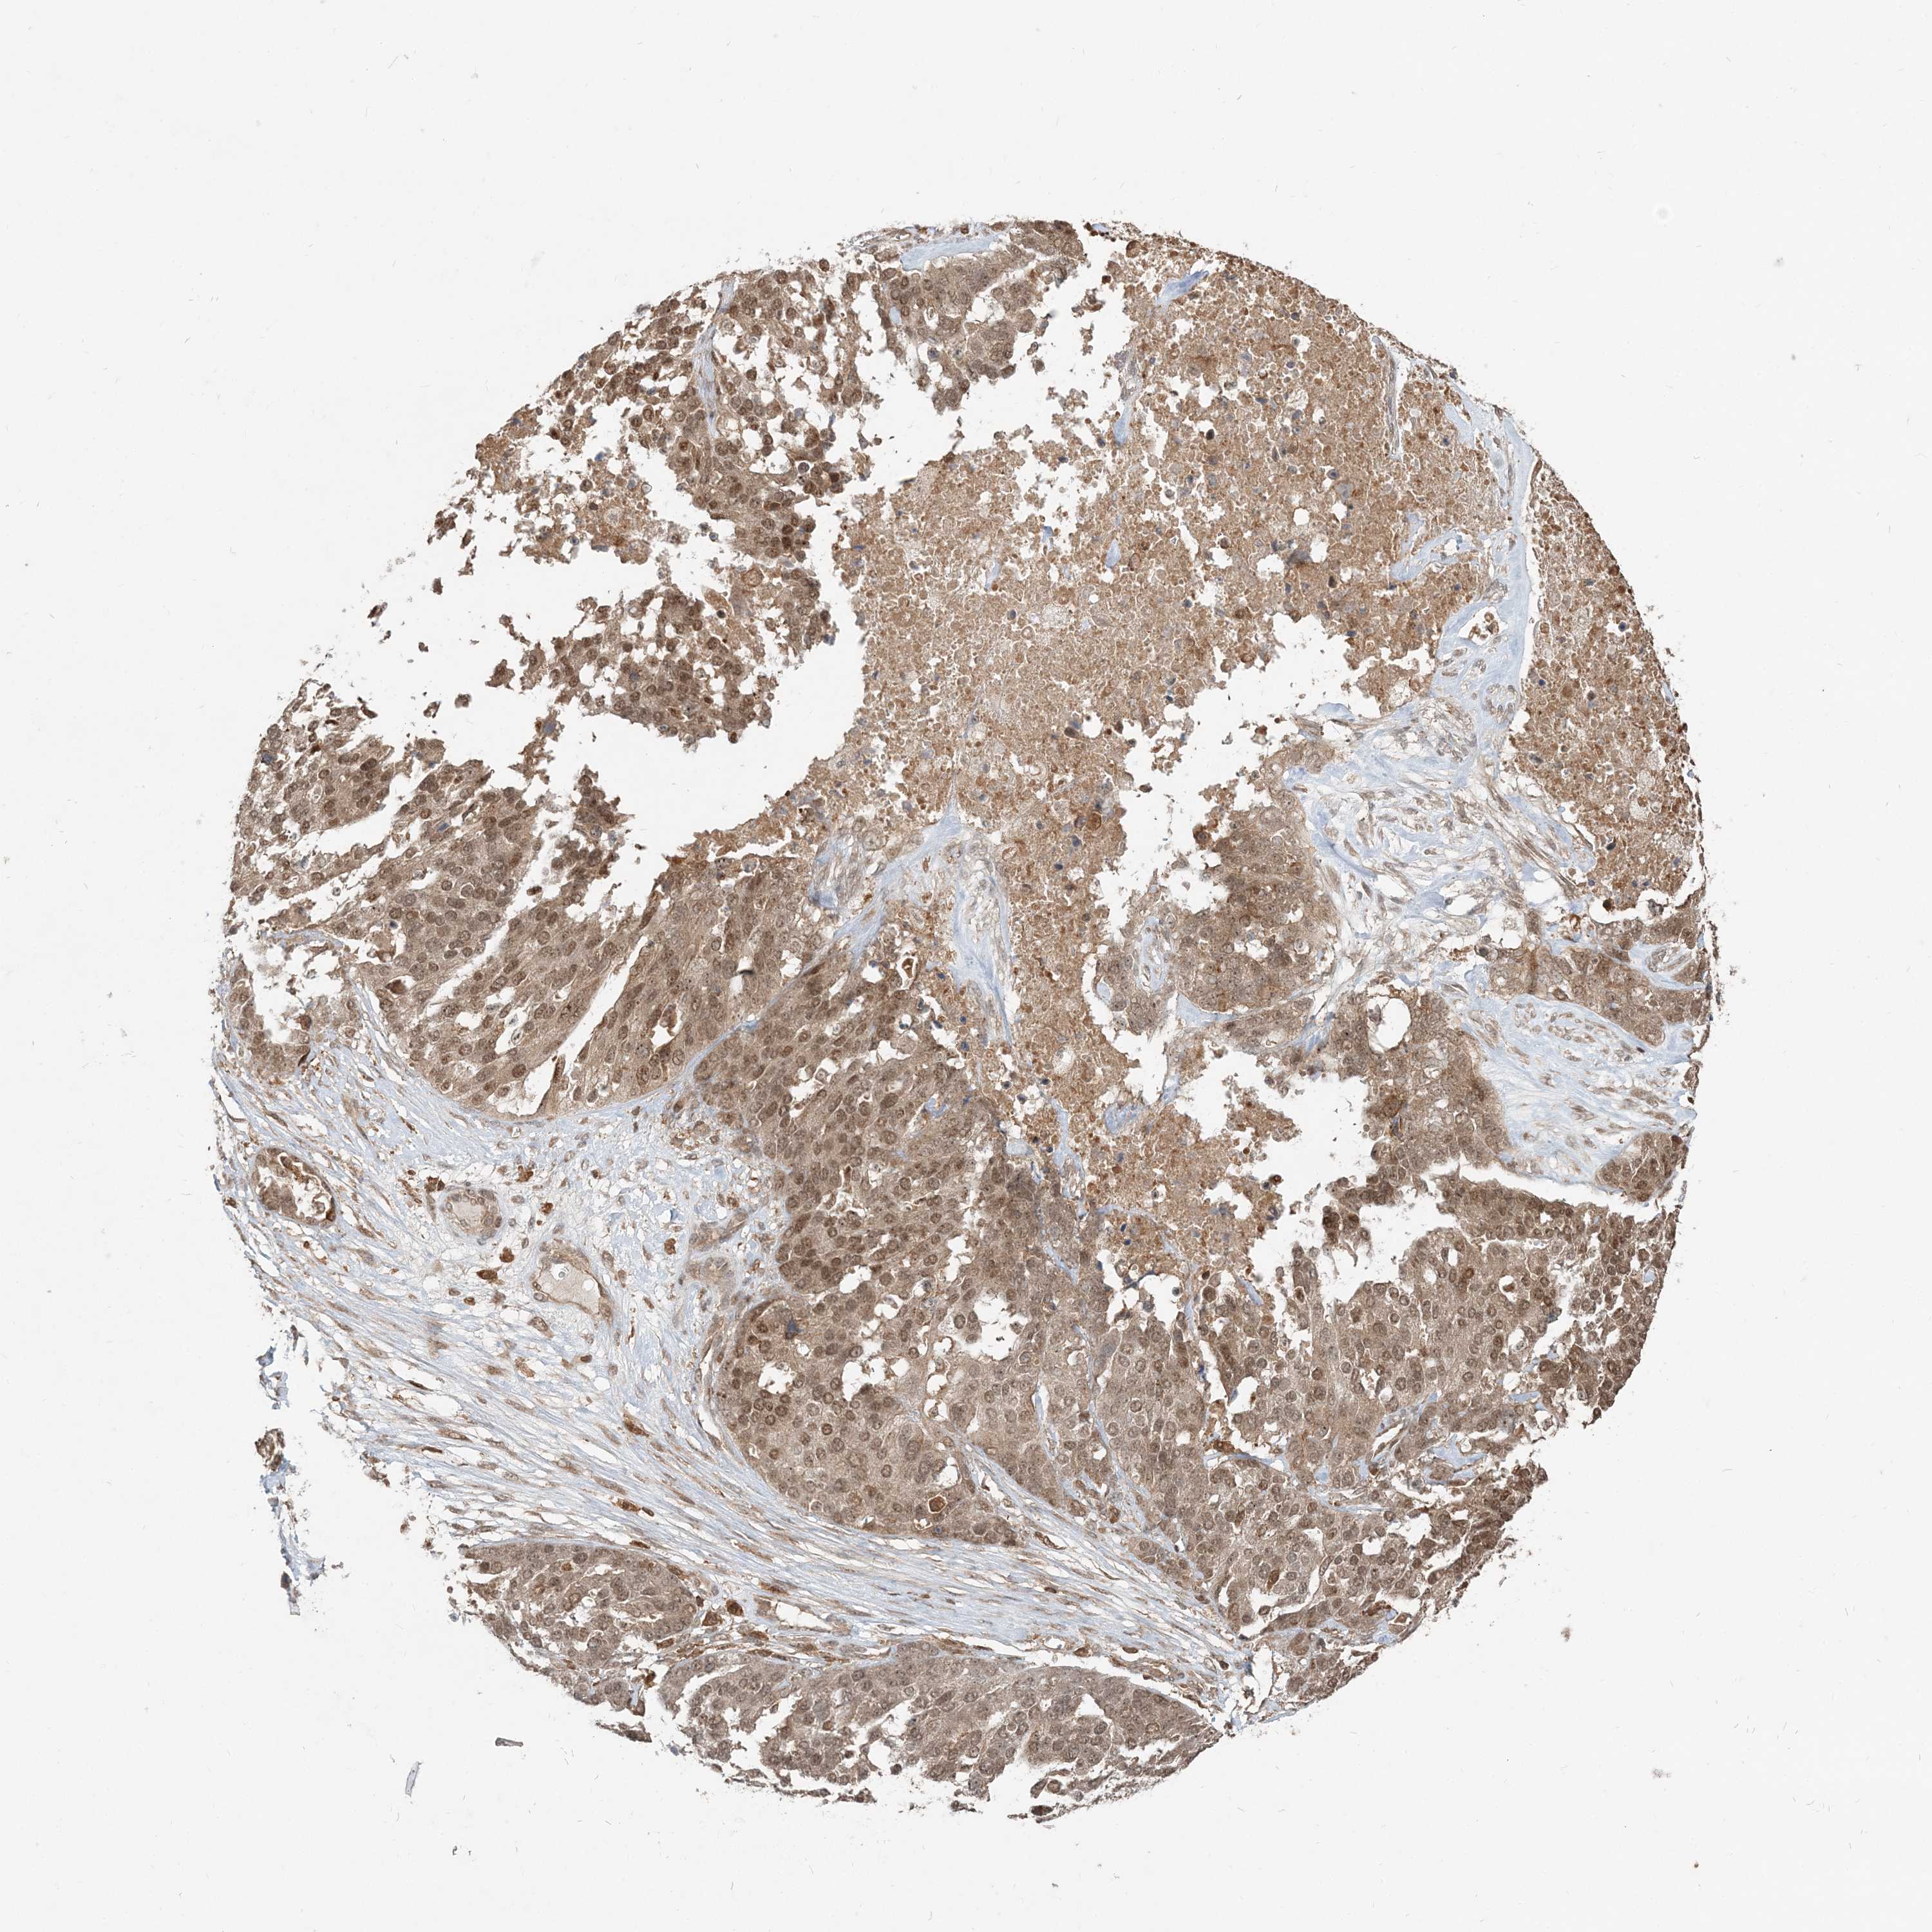

OVARIAN CANCER - Protein expressioni

A mouse-over function shows sample information and annotation data. Click on an image to view it in a full screen mode. Samples can be filtered based on level of antibody staining by selecting one or several of the following categories: high, medium, low and not detected. The assay and annotation is described here.

Note that samples used for immunohistochemistry by the Human Protein Atlas do not correspond to samples in the TCGA dataset.

Antibody stainingi

Antibody staining in the annotated cell types in the current human tissue is reported as not detected, low, medium, or high, based on conventional immunohistochemistry profiling in selected tissues. This score is based on the combination of the staining intensity and fraction of stained cells.

Each image is clickable and will lead to virtual microscopy that enables deeper exploration of all samples and also displays staining intensity scores, fraction scores and subcellular localization as well as patient and tissue information for each sample.

Antibody HPA076632

Antibody CAB037112

Cystadenocarcinoma, serous, NOS

Cystadenocarcinoma, mucinous, NOS

Carcinoma, endometroid

Carcinoma, NOS